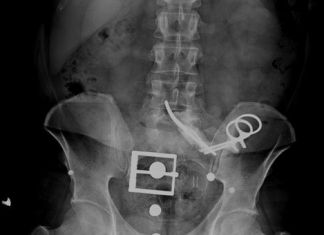

23 Yıl Karnında Makasla Yaşadı

Adapazarı'nda bir adam 23 yıl önce dalağını aldırmak için ameliyat olmuştu. Aradan geçen 23 yıl sonra, 1 Nisan'da bel ağrısı şikayetiyle Sakarya Üniversitesi Eğitim ve Araştırma Hastanesi'ne giden...